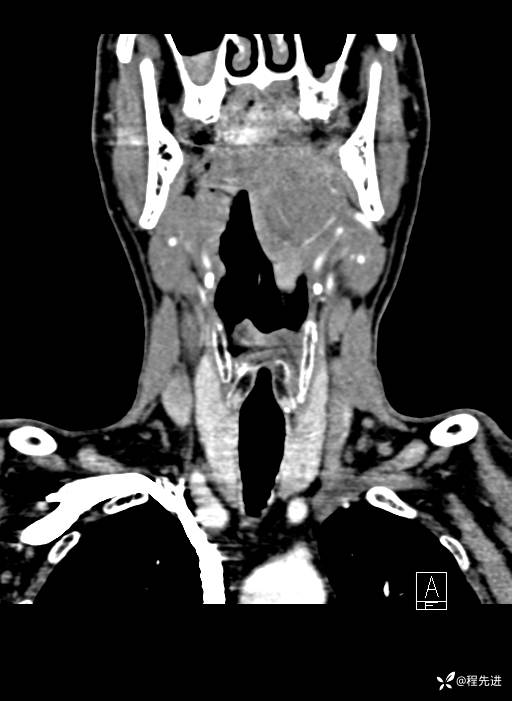

CT平扫:

CT增强:

静脉期:

增强冠矢状位重建: